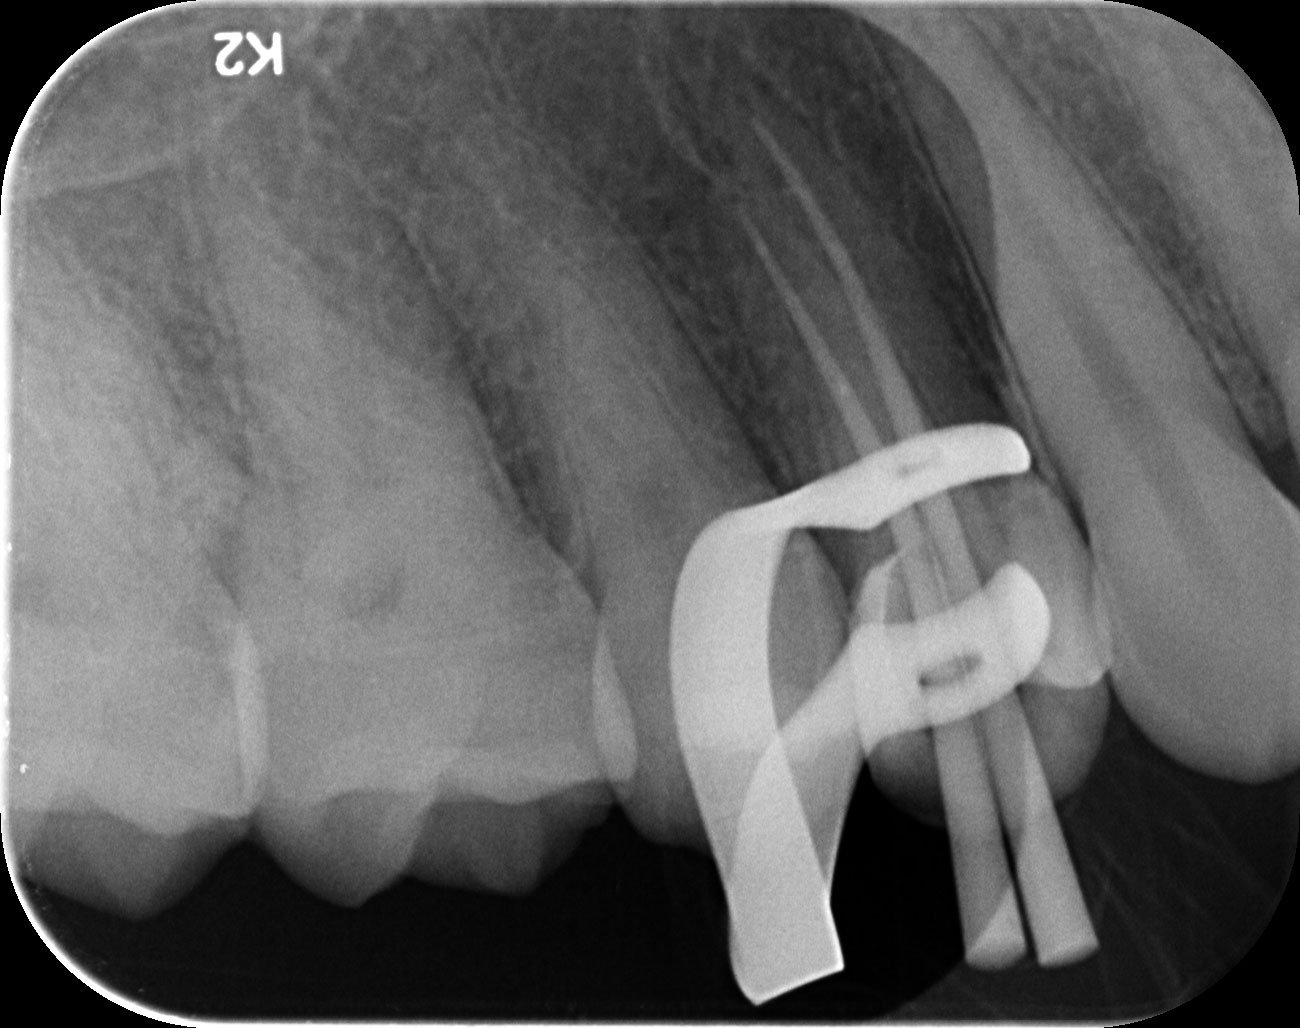

Dantų kanalų gydymas